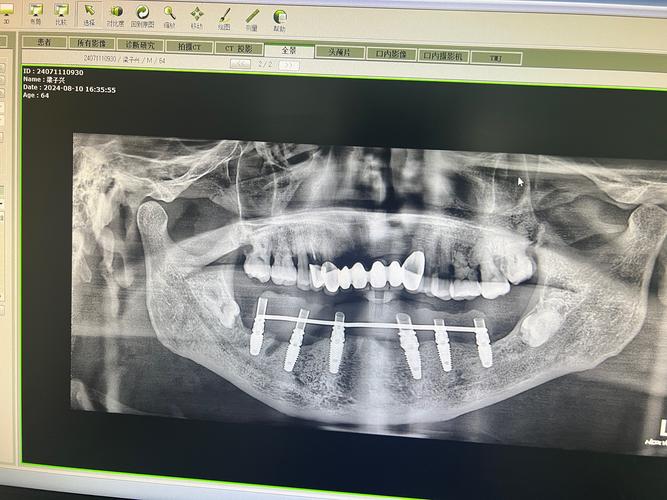

- 全景片(曲面断层片): 最常用,能一次性显示全口牙齿、牙槽骨、颌骨、上颌窦、下颌神经管等的大致情况,但它是二维影像,存在重叠和放大失真,对骨量评估精度有限。

- 锥形束CT(CBCT): 这是种植牙术前评估的“金标准”! 它能生成三维立体影像,提供牙槽骨高度、宽度、密度的精确数据,清晰显示神经管、上颌窦等关键结构的立体位置和形态,对于复杂病例(骨量不足、后牙区种植、即刻种植等),CBCT是必不可少的。